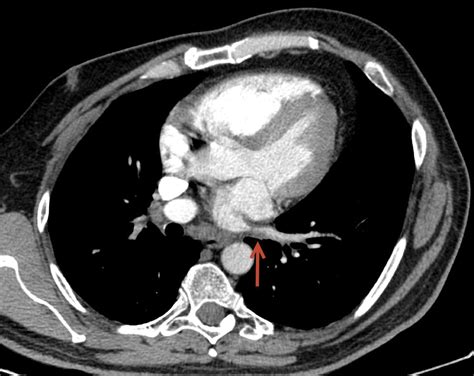

Computed Tomography (CT) Scan Provides detailed images of the pulmonary veins and surrounding structures, helping to identify the location and extent of stenosis.

These diagnostic tests help healthcare providers determine the presence and severity of Pulmonary Vein Stenosis, guiding the development of an appropriate treatment plan.